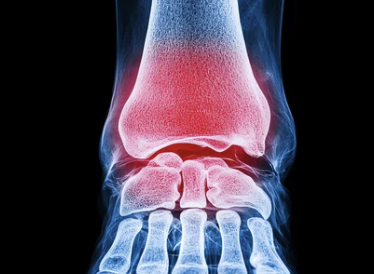

발목 인대파열은 발목을 무리하게 비틀거나 넘어지면서 발생할 수 있는 흔한 손상입니다. 발목이 갑자기 접히거나 외부 충격을 받을 때 인대가 늘어나거나 찢어지면서 통증과 부기가 생기고, 방치할 경우 발목이 불안정해지며 장기적인 불편으로 이어질 수 있습니다. 이번 글에서는 발목 인대파열의 증상과 치료법, 재활 방법까지 자세히 알아보겠습니다.

발목 인대파열은 발목을 안정적으로 유지하는 인대가 손상된 상태를 의미합니다. 인대는 관절의 움직임을 지탱해 주는 강한 섬유조직인데, 갑작스러운 충격이나 부상으로 인해 손상을 입을 수 있습니다.

2. 발목 인대파열의 주요 증상: 부기와 통증을 넘어서

발목 인대파열 시, 초기 증상은 다른 발목 염좌와 비슷할 수 있지만 통증의 강도와 지속성이 일반 염좌보다 강합니다. 이를 조기에 인지하고 대처하는 것이 중요합니다.

• 부기와 멍: 손상 직후 발목 주위가 붓고, 시간이 지나면서 멍이 들 수 있습니다.

• 강한 통증: 발목을 움직이거나 디딜 때 참기 어려운 통증이 발생합니다.

• 발목 불안정성: 발목이 흔들리거나 안정감을 잃고 약해진 느낌이 들 수 있습니다.

• 움직임 제한: 인대가 찢어진 상태에서 발목을 움직이기 어렵거나 통증 때문에 제한됩니다.